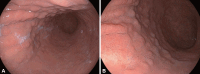

Atrophic gastritis is primarily caused by Helicobacter pylori infection and autoimmune mechanisms. In South Korea, where H. pylori infections remain highly prevalent, standardized guidelines for the use of serological testing or biopsies for diagnosing autoimmune gastritis (AIG) have not been developed. Recently, as H. pylori infection rates have declined and trends associated with gastric cancer and gastric neuroendocrine neoplasms (gNENs) have shifted, interest in AIG has increased, particularly in Asia. However, AIG diagnoses are often delayed owing to a lack of suspicion; even when AIG is considered, the limited understanding of the disease hampers its accurate diagnosis. Furthermore, the absence of established treatments and standardized follow-up protocols pose significant challenges for patient management. The loss of gastric acid secretion, a critical component of digestive function, and destruction of the gastric corpus mucosa are caused by autoimmune mechanisms, leading to incomplete protein digestion, micronutrient deficiencies, gut microbiota imbalances, and elevated gastrin levels that eventually contribute to neoplastic lesions, such as gNENs and gastric cancer. Although AIG is an immunerelated gastrointestinal disorder, it intersects with various disciplines, including pathology, genetics, microbiology, endocrinology, hematology, and oncology, and many unresolved issues remain in these areas. Research to address unanswered questions about the disease pathogenesis, the relationship between AIG and H. pylori, appropriate diagnostic methods and the risk of gastric neoplasms has previously been published. This review provides an overview of the current findings and explores unanswered questions surrounding AIG to help elucidate its complex pathogenesis, clinical implications, and potential management strategies.